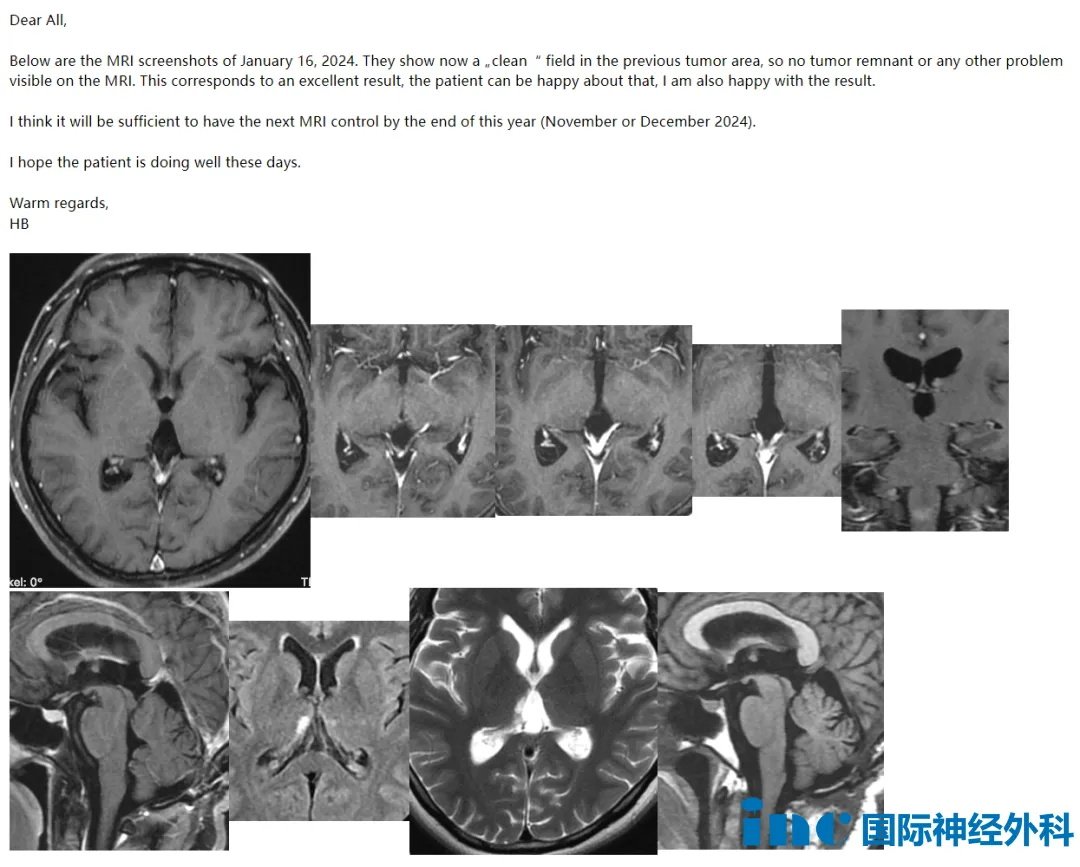

术后半年复查时,巴教授查看了晴晴的复查影像后回复:

“以下是2024年1月16日的核磁共振截图。这些截图显示,以前的肿瘤区域现在是一个"干净"的区域,因此核磁共振成像上看不到肿瘤残余或其他问题。这相当于一个很好的结果,病人可以为此感到高兴,我也对这个结果感到高兴。我认为在今年年底(2024年11月或12月)进行下一次核磁共振检查就足够了。希望病人最近一切都好。”